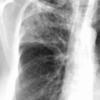

Case 2  Lingular pneum Lat

Date: 04/17/2005

Views: 6951